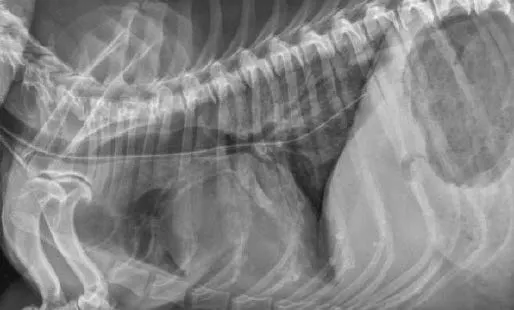

Tubes can be accidentally misplaced in the trachea (Figure 2A), nasopharynx, or nasal cavity, and subsequent feeding may result in aspiration pneumonia; therefore, appropriate placement should be confirmed before feeding is initiated. Various inexpensive methods can help verify tube location: laryngoscopic visualization of the tube entering the esophagus; suction to verify negative pressure; air infusion while auscultating the abdomen for borborygmus; infusion of sterile saline or nonionic contrast medium (Figure 2B), which sometimes elicits a cough with tracheal placement; or pH assessment of fluid aspirated from the tube.

Inadvertent placement of an NG tube in the trachea and bronchus of a miniature dachshund (11 years of age). This dog had a severe pulmonary interstitial pattern secondary to infusion of 20 mL of sterile saline through the tube; it had no cough reflex during infusion (A). After injection of 3 mL of iohexol 240, positive contrast medium outlined the alveoli, particularly in the caudodorsal thorax, confirming tube misplacement (B). The following day, radiography confirmed that contrast medium and saline had been cleared from the lungs.